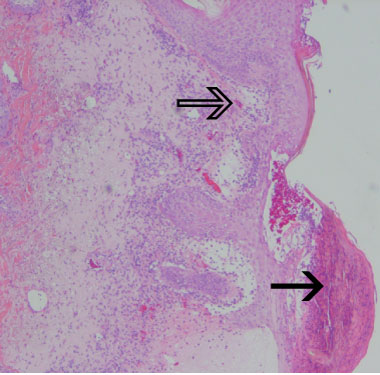

Blood tests returned the following results: C-reactive protein 135 mg/L (reference range [RR], < 12 mg/L); white blood cells 17.2 × 109/L (RR, 4.0–11.0 × 109/L); neutrophils 15.8 × 109/L (RR, 2.0–7.5 × 109/L); and eosinophils 0.79 × 109/L (RR, 0.04–0.40 × 109/L). A skin biopsy showed neutrophil-containing spongiotic pustules in the epidermis and a mixed cellular infiltrate with oedema in the papillary dermis, consistent with acute generalised exanthematous pustulosis (Box 2).

The criteria for diagnosis of AGEP are defined by the EuroSCAR score.11 Features of the condition include acute onset of small, sterile, non-follicular pustules on erythematous skin beginning in intertriginous areas or on the face; systemic signs, with fever over 38°C (in a typical course, an acute rash appears within 1–2 days and resolves by skin desquamation within 4–10 days after discontinuation of the causative agent); and neutrophilia, in the setting of a consistent histological pattern.11 The patient described here had a classic drug-induced AGEP with typical morphology, course and histology and a validation score of 12 points (the range for definite AGEP is 8–12).11